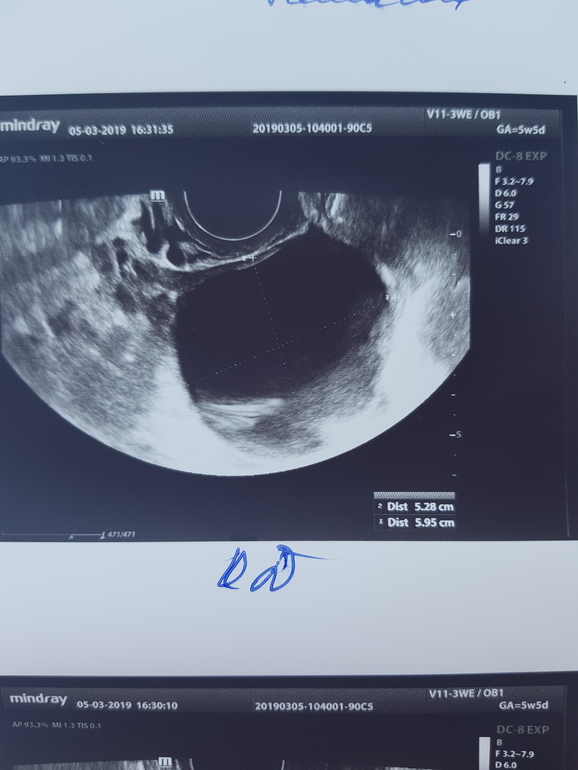

По месячным 5нед6дней, но овуляция была на неделю позже и срок меньше. Вчера была на узи, чтобы исключить внематочную. Нашли плодное яйцо 4,3 мм и большую гематому рядом 19,1 на 5,6 мм. И еще кисту желтого тела 5 см. Узист напугала страшно. Угроза выкидыша, полный покой, никаких каблуков и секса. Я отправила узи врачу, сказал подходить в четверг, до четверга ничего не предпринимать.

Вот фото узи

Киста